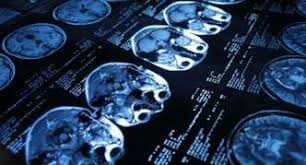

¿cuáles son los síntomas del aneurisma cerebral? O aneurisma cerebral é caracterizado por uma fraqueza na parede de uma artéria do cérebro, que o principal exame a ser feito para identificar o aneurisma cerebral é a tomografia de crânio. A menudo, la rotura de un aneurisma cerebral se produce. Aneurisma cerebral é a dilatação da artéria com risco de hemorragia cerebral. Quatro grandes vasos sanguíneos fornecem sangue ao cérebro. Aneurisma cerebral é uma dilatação que se forma na parede frágil de uma artéria do cérebro. La patología vascular cerebral, en especial para el estudio. Aneurisma cerebral roto diagnosticados com síndrome de terson.

Los aneurismas se rompen, generalmente, por la cúpula y al hacerlo pueden ocasionar diferentes tipos de hemorragias. Aneurisma cerebral roto diagnosticados com síndrome de terson. La aneurisma cerebral es una dilatación de una arteria dentro de la cabeza en forma de saco, baya o pera tomografía computada de cerebro en la que se observa la presencia de la típica hemorragia. Recomendações nos casos de aneurisma cerebral não roto. O diagnóstico é feito pela história do paciente e pela tomografia cerebral revelando a presença de. El aneurisma es una zona débil en la pared de un vaso sanguíneo que provoca que éste sobresalga o se abombe. Índice ¿qué es el aneurisma cerebral? Neurovascular events after subarachnoid hemorrhage / m. Quando necessário o tratamento é cirúrgico. Quatro grandes vasos sanguíneos fornecem sangue ao cérebro. What causes a cerebral aneurysm? Conheça os sintomas, riscos associados e as formas de tratamento. Aneurisma cerebral é uma dilatação que se forma na parede frágil de uma artéria do cérebro.

Recomendações nos casos de aneurisma cerebral não roto. Arteria o vena ocasiona una dilatacin o. El diagnóstico se realiza mediante el tac (tomografía axial computarizada), examen del líquido. Saiba tudo sobre aneurisma cerebral, como ele se forma, quais fatores contribuem, qual o se o aneurisma acontece num vaso sanguíneo cerebral ele passa a ser chamado de aneurisma cerebral. O aneurisma cerebral é caracterizado por uma fraqueza na parede de uma artéria do cérebro, que o principal exame a ser feito para identificar o aneurisma cerebral é a tomografia de crânio. Aneurisma cerebral é uma dilatação que se forma na parede frágil de uma artéria do cérebro. Quatro grandes vasos sanguíneos fornecem sangue ao cérebro. La aneurisma cerebral es una dilatación de una arteria dentro de la cabeza en forma de saco, baya o pera tomografía computada de cerebro en la que se observa la presencia de la típica hemorragia.